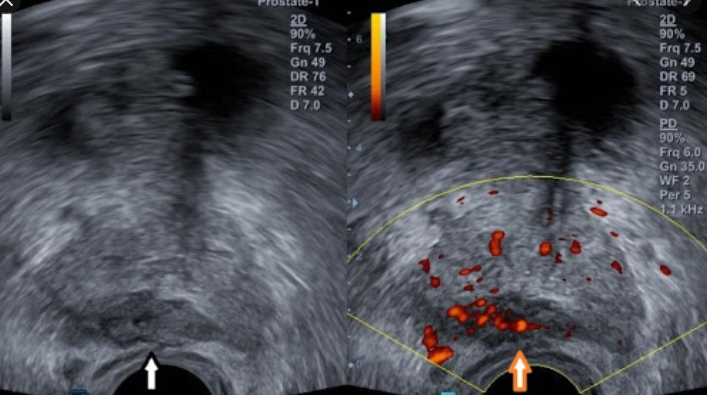

전문의와 문진을 하거나, 신체검사를 하는방법이 있습니다. 또한 소변검사도 진행합니다. 또한 요류 및 잔료량 검사와 압력 요류검사 등 여러가지가 있고, 방광경 검사와 경직장 초음파검사 또한 실시할 수 있습니다.